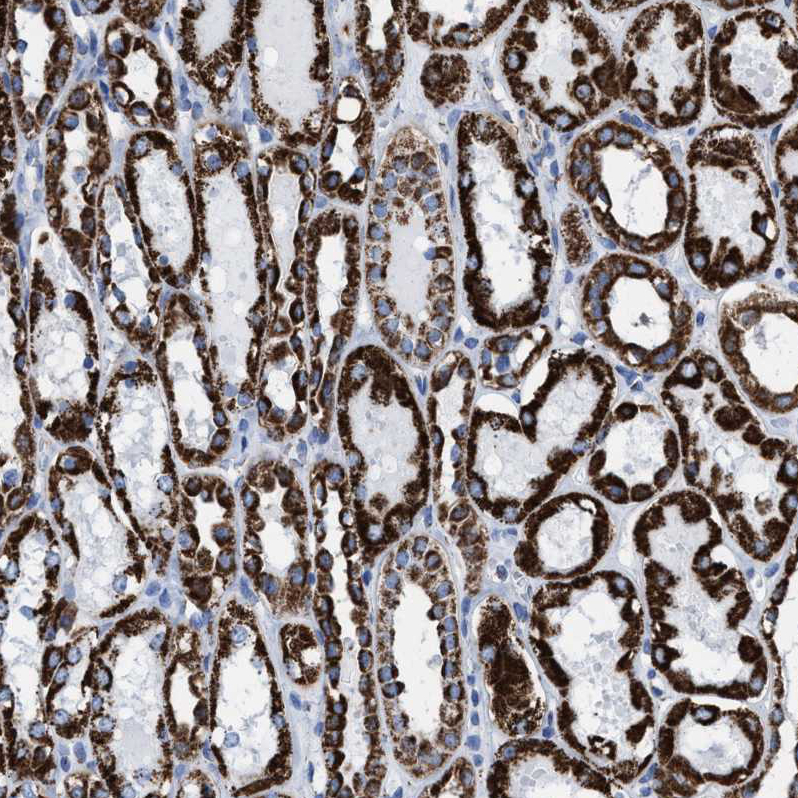

Immunohistochemical staining of human gastrointestinal, heart muscle, kidney and liver using Anti-ECHS1 antibody HPA021995 (A) shows similar protein distribution across tissues to independent antibody HPA022476 (B).